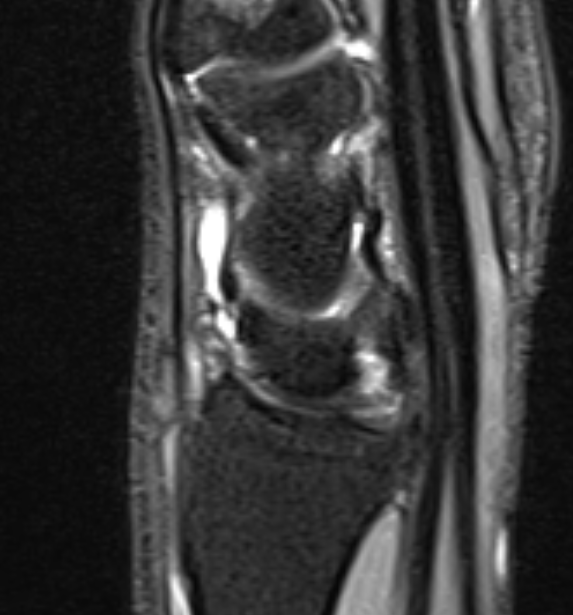

MRI

Dorsal ganglion arising from scapholunate joint

Dorsal ganglion arising from scapho-lunate joint

Volar ganglion